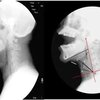

“テノールとソプラノ各1名が,音高変化させて歌唱する際の声道形状をrtMRIで撮像し,どのような制御を行っているのか検討した”

“5度跳躍進行において,テノールは上行で口を開き,軟口蓋を下げ,喉頭を下降させ,頸椎を後弯させていた.そしてこの制御は,上行と下行で同じ度合いで用いられていた”

“一方ソプラノでは,上行では上を向いて口を開き,咽頭を広げ,頸椎を後弯させ,喉頭を上昇させていたが,下行では口を閉じることで制御を行っていた.つまり,ソプラノは上行と下行で声道形状の制御が異なっていた”

“テノールとソプラノの結果から,口の開き度合いと頸椎の後弯度合いは共に音高の調節に必要な制御であると思われる”